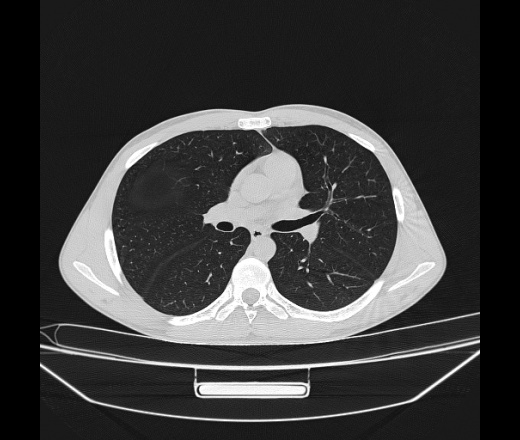

Молодой парень 18 лет, призывник, при прохождении ФЛС на верхушек левого легкого выявили очаги средней интснисвности с нечеткими контурами, тяжи. Сделали бок и томограммы 6-7-8. Везде описывают как очаговый твс. Вижу только перибронхиальный фиброз. Что за изменения в бронхах, указано нижи стрелками, тоже перибронхиальный?

Не стал бы говорить об очагах. Акцентировал бы не на фиброзе, а на тракционных бронхоэктазах. Не обязательно они результат tbc бронхов, но проверить не помешает.

Иван, пациент ведь уже "направлен с ОПТД", так?surprise Возвращайте его назад с заключением о возможном микобактериозе. Остаточные поствоспалительные ( посттуберкулёзные?) в дифряд.Очаговый твс с неясной активностью они уже себе "нарисовали", как я поняла.

+1 за микобактериоз.